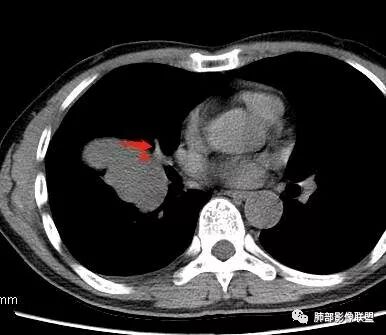

南边:病灶边界清,提示侵袭性弱,膨胀生长为主;这时候我们提示病灶不应该是支气管关系密切,提示间叶来源或胸膜来源

深分叶,警惕恶性

常规考虑:1、肉瘤首先考虑

2、胸膜孤立性纤维瘤待排

南边:结果:肉瘤